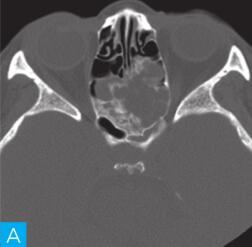

CT检查:检查设备为16层CT,病人采取仰卧位,扫描范围包括双侧鼻窦。扫描参数:层厚2.5mm,120kV,150mA,矩阵512×512。观察图像:软组织窗窗宽300HU,窗位60HU;骨窗窗宽2000HU,窗位400HU,见图1。

图1 鼻窦CT:A. CT横断面(骨窗);B. CT横断面(软组织窗);C. CT冠状面(骨窗);D. CT冠状面(软组织窗)

答案A 解析:结合CT横轴位及冠状位图像,该病变位于后组筛窦,不难判断。

答案D 解析:该病例病变周围骨质在原有后组筛窦结构基础上出现轻度的骨质膨胀性改变,周围骨质可见明显硬化,故D为最佳答案。

CT平扫示后组筛窦区见轻度膨胀性骨质破坏,内部密度混杂,可见斑片状、分隔状骨质密度影,部分呈磨玻璃改变,病变边缘清晰,可见薄层骨壳及硬化边。

发现病变较为容易,主要分析其病变的良恶性。本病例基本征象为病变区域呈轻度膨胀性骨质破坏,邻近骨质呈轻度压迫性骨质吸收,边缘可见硬化边,提示病变慢性进展过程,病变内部密度欠均匀,以软组织密度以及磨玻璃样高密度为主。

对于本病例来说,病变定位不困难,病变主体位于后组筛窦区。

本病例CT上特点为轻度膨胀性压迫性骨质吸收,边缘骨质见硬化边,呈薄层骨壳表现,提示肿瘤良性可能;病变内部密度不均匀,可见骨性间隔及斑片状磨玻璃骨性密度影,提示病变可能为骨纤维源性肿瘤或肿瘤样病变。